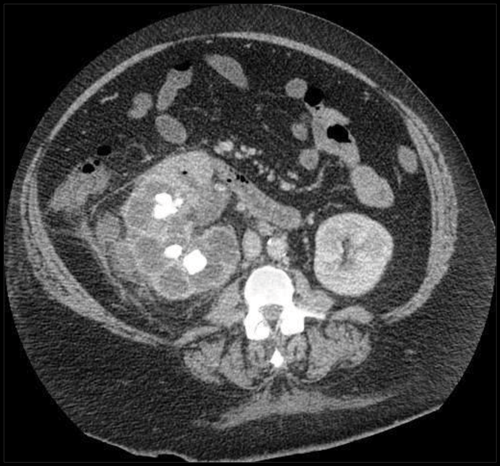

A 42-year-old male presented with sepsis, fatigue and abdominal pain. He had a previous history of renal calculi. A contrast CT was performed to ascertain the cause of the pain.

1. Describe the abnormalities seen on the CT.

2. What is the classic description given to this appearance?

3. What is the diagnosis?

4. What treatment is usually required?

Case 9

- There is right hydronephrosis and perinephric fat stranding adjacent to the right kidney. Air is seen in the collecting system and there are multiple calculi in the right kidney.

- The appearance has a description of a ‘bear’s paw’.

- The diagnosis is xanthogranulomatous pyelonephritis. This is seen in a chronically infected, obstructed kidney, and 80% of cases have renal calculi. The commonest causative organisms are Proteus and E coli. It is often associated with diabetes, or seen in immunocompromised patients. It usually affects the whole kidney, but 15% of cases can be focal.

- Antibiotics should be given, but surgical treatment with nephrectomy is usually required. The affected kidney is usually non-functioning, and patients are often systemically unwell due to the chronic nature of the condition.